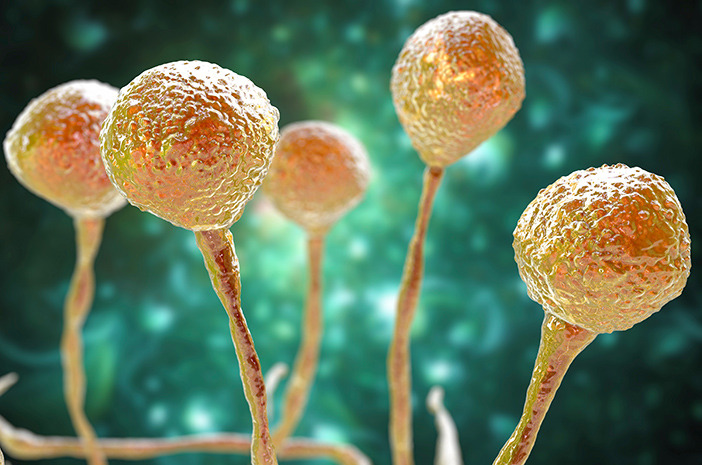

يُعرف مرض الفطر الأسود طبيا باسم داء الفطار العفني، وهو عدوى فطرية خطيرة تسببها فطريات تنتمي إلى فصيلة العفن وتوجد بشكل طبيعي في البيئة المحيطة مثل التربة والمواد العضوية المتحللة والهواء. تدخل هذه الفطريات إلى جسم الإنسان غالبا عن طريق الاستنشاق عبر الأنف أو من خلال الجروح الجلدية المفتوحة، ثم تبدأ في النمو داخل الأنسجة المصابة.

يتميز المرض بقدرته على غزو الأوعية الدموية، ما يؤدي إلى ضعف تدفق الدم وموت الأنسجة المصابة، وهو ما يفسر ظهور اللون الأسود في بعض الحالات المتقدمة. يظهر المرض بشكل أكبر لدى مرضى السكري غير المنتظم أو من يتلقون أدوية مثبطة للمناعة أو بعد الإصابة بأمراض فيروسية شديدة، وتزداد خطورته بسبب سرعة انتشاره داخل الجسم خلال فترة قصيرة إذا لم يعالج مبكرا.